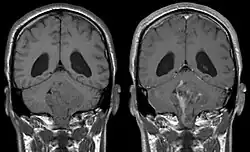

• hydrocephalus

Ependymomas make up about 5% of adult intracranial gliomas and up to 10% of childhood tumors of the central nervous system (CNS). Their occurrence seems to peak at age 5 years and then again at age 35. They develop from cells that line both the hollow cavities of the brain and the central canal containing the spinal cord, but they usually arise from the floor of the fourth ventricle, situated in the lower back portion of the brain, where they may produce headache, nausea and vomiting by obstructing the flow of cerebrospinal fluid. This obstruction may also cause hydrocephalus. They may also arise in the spinal cord, conus medullaris and supratentorial locations.[7] Other symptoms can include (but are not limited to): loss of appetite, difficulty sleeping, temporary inability to distinguish colors, uncontrollable twitching, seeing vertical or horizontal lines when in bright light, and temporary memory loss. It should be remembered that these symptoms also are prevalent in many other illnesses not associated with ependymoma.

Intracranial ependymomas, including supratentorial and posterior fossa, make up 90% of ependymomas in children. The supratentorial region is the upper brain region, or cerebrum, and contains the lateral and third ventricles. The posterior fossa, or infratentorial, is behind or below this region in the area of the brainstem and cerebellum and contains the fourth ventricle. A majority of intracranial pediatric ependymomas are in the posterior fossa.[15] Patients with intracranial ependymomas typically present with increased intracranial pressure that results in headaches, dizziness, nausea, and vomiting. The third location of ependymomas is within the central canal of the spinal cord. Spinal ependymomas comprise about 65% of adult ependymomas and most often occur in the lumbosacral region.[13] Patients with spinal ependymomas can present with back pain, numbness or weakness in the limbs, and urinary or bowel problems.